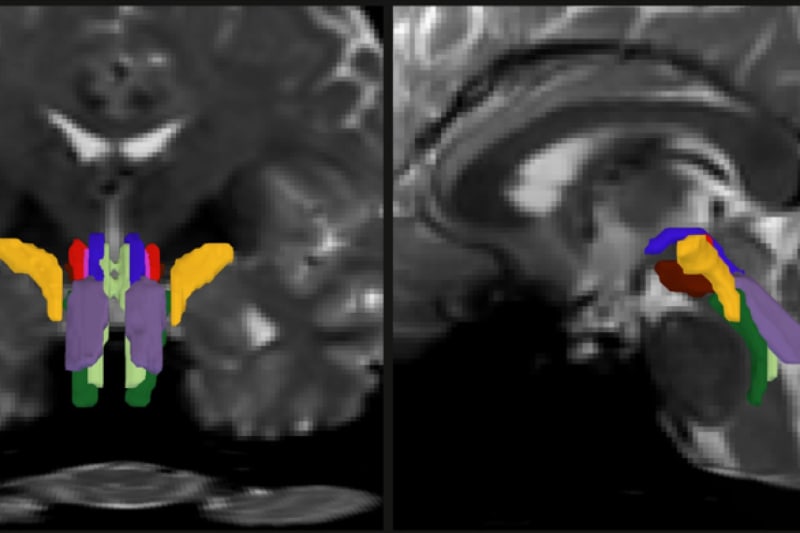

MIT graduate student Mark Olchanyi has created software that does what medical imaging couldn't do before: clearly identify eight distinct nerve bundles in the brainstem. This thumbnail-sized region controls everything from breathing and heartbeat to consciousness itself, but until now it's been nearly impossible to see what's happening inside when something goes wrong.

Olchanyi's solution combines artificial intelligence with existing MRI technology. The BrainStem Bundle Tool (BSBT) traces nerve fibers from nearby brain regions down into the brainstem, then uses a neural network to distinguish individual bundles. He trained it on 30 brain scans and validated it against actual dissections of donated brains.